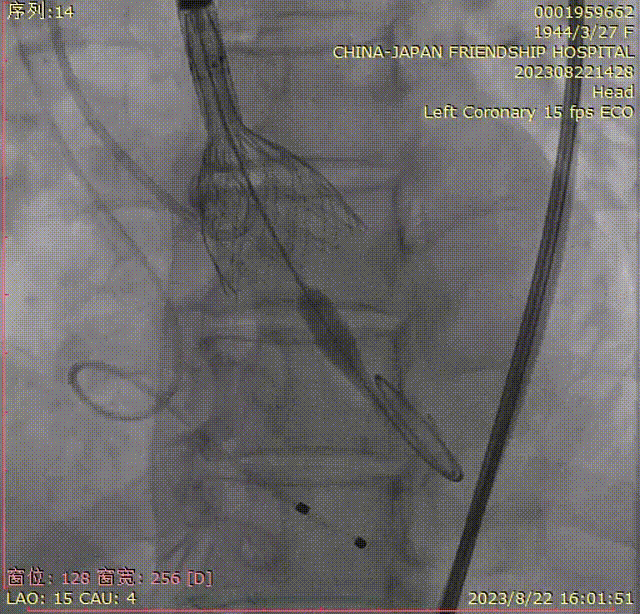

特别值得一提的是,团队在两个脑保护装置中都发现了栓子的掉落。这一发现表明SENTINEL可以成功地捕捉到手术操作过程中产生的碎片,从而有效地避免了脑卒中的发生。

【可见脑保护装置捕获碎片】